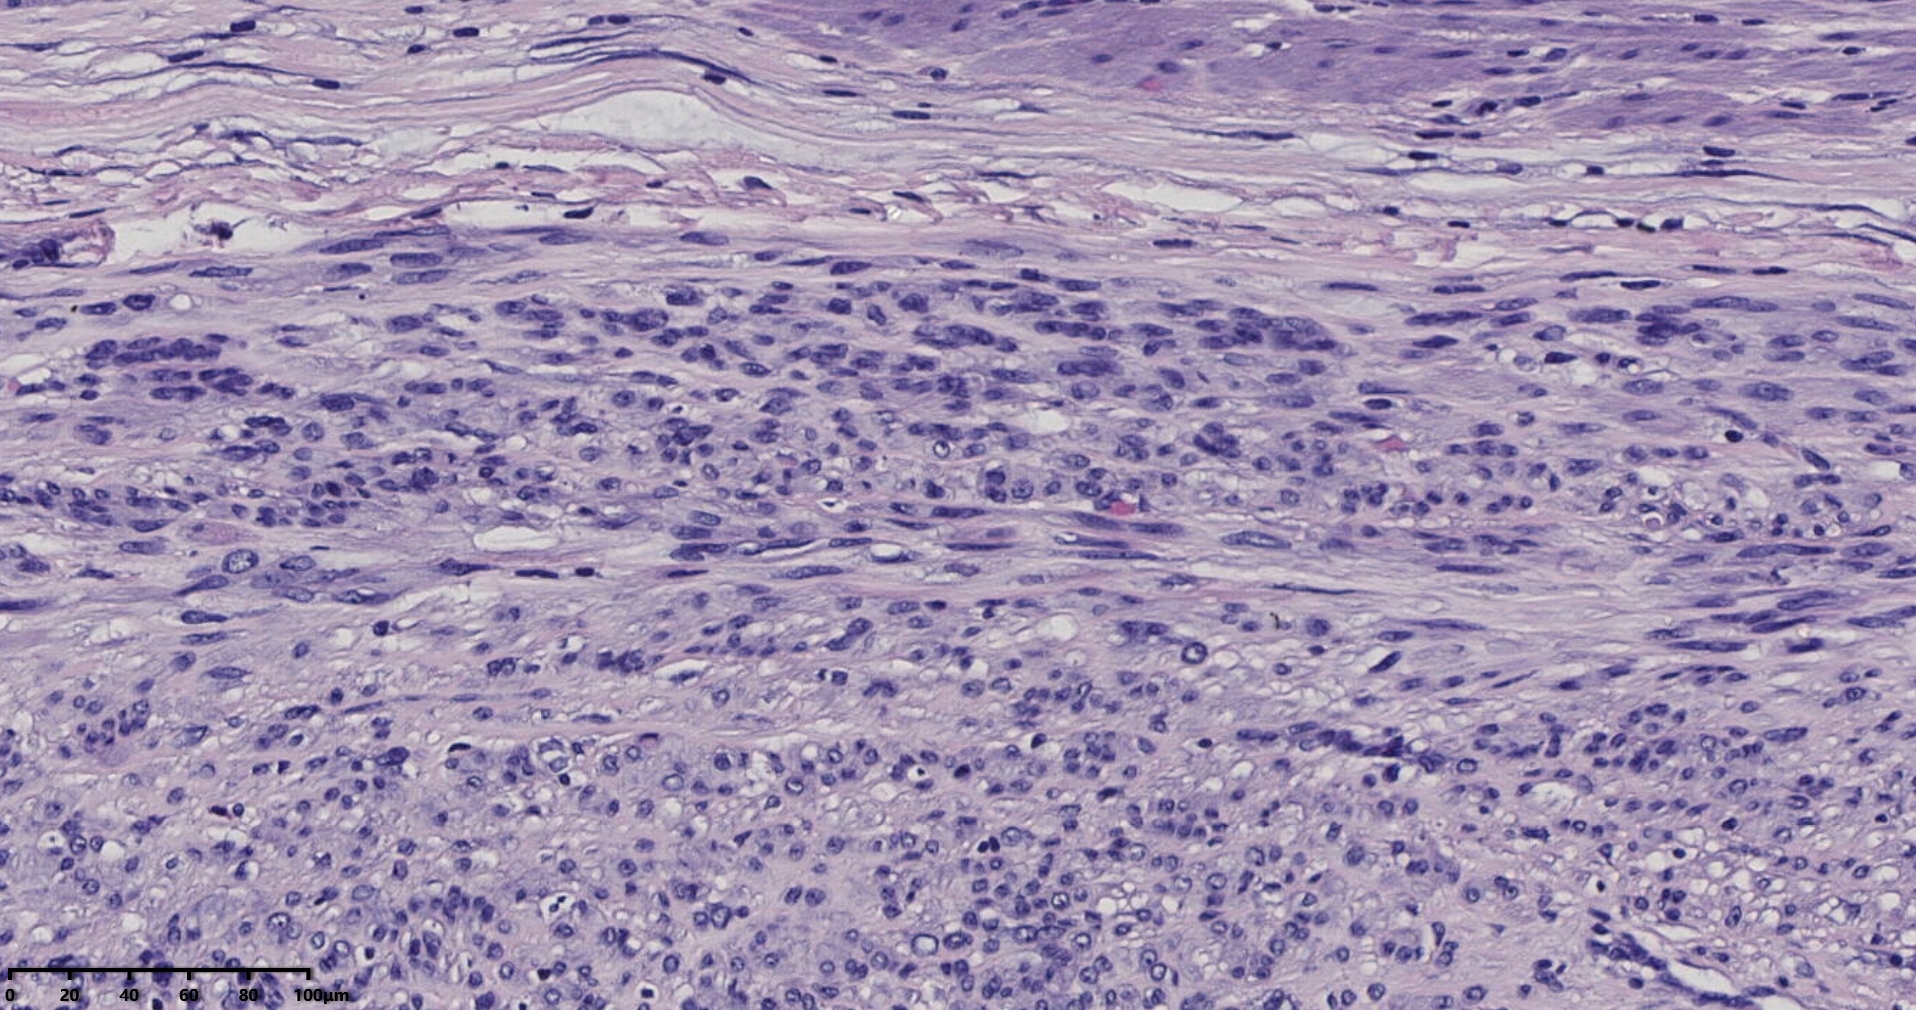

镜下所见小肿物无特殊,大肿物瘤细胞密集,中心区有变性、坏死,瘤细胞核有异型性。大肿物补充取材,发现,部分区域切面灰黄,这个区域,瘤细胞更密集,异型性更显著。肿物边缘有薄层正常平滑肌组织被覆,靠近边缘瘤细胞最密集,局部瘤组织内小血管较丰富。